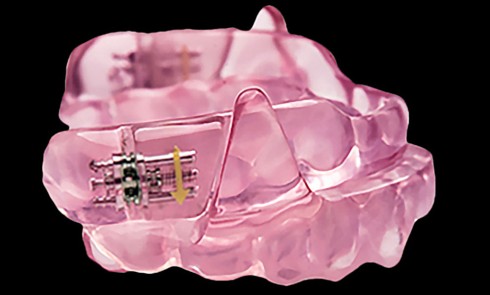

Place des OAM dans le traitement du Sahos [1 2 3] Définition des OAM Une orthèse est un dispositif médical amovible qui...Maladie de Parkinson et prise en charge bucco-dentaire